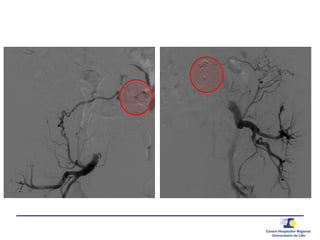

Embolisation transartérielle

• Angiographie

• Embolisation Type 2

• Embolisation iliaque interne + jambage

d’extension iliaque